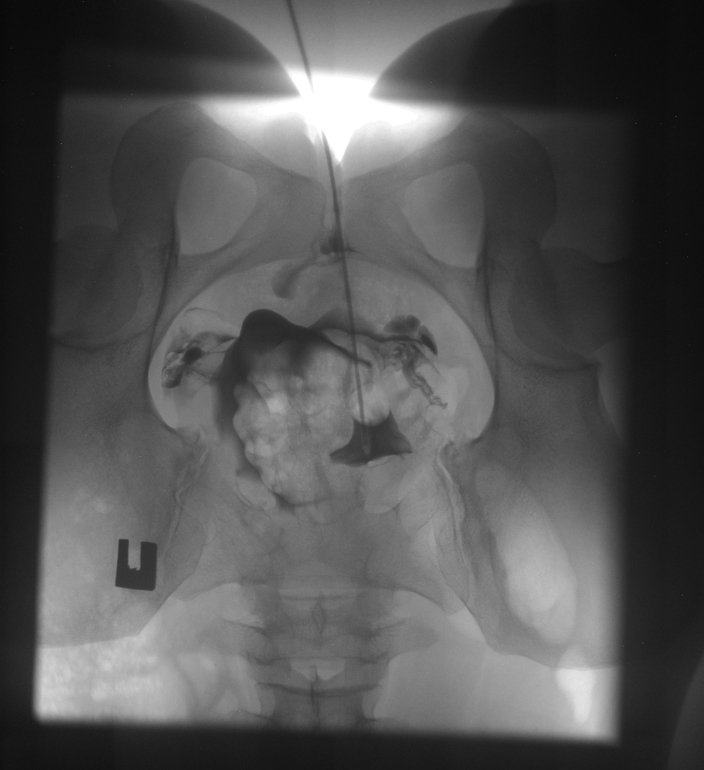

Моя ГСГ (МСГ)

ГСГ, ЭХО, МСГ, ФертилоскопияНу что, девочки, сегодня прошла я эту процедуру, такую долгожданную еще с марта.

Результат: идеально проходимые трубы, матка без патологий !

Таких идеально проходимых труб по словам гинеколога он давно не видел.

Только влил раствор, он сразу прошел. Влил- прошел. И так три раза.

Матка почему то отклонена чуть влево, без видимых причин .